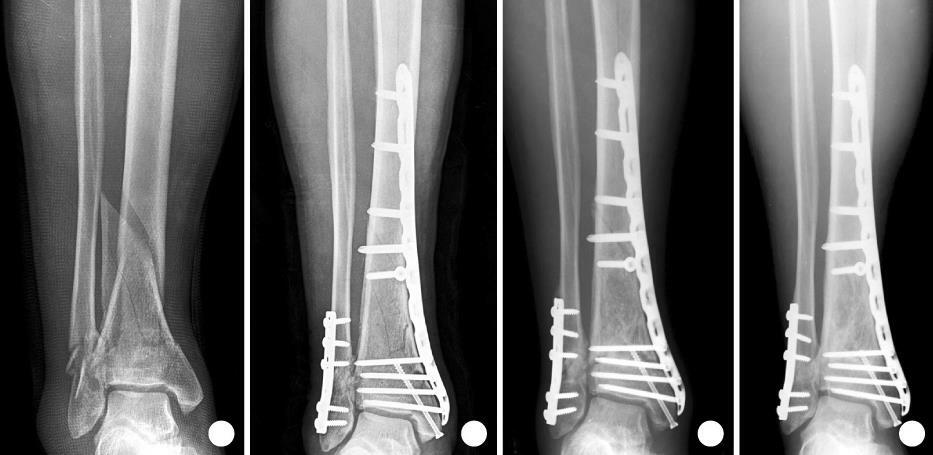

Переломы нижней трети голени

Виды переломов

Диагностика в т. ч. инструментальная (рентген, МРТ, КТ)

Виды лечения (оперативное, консервативное)